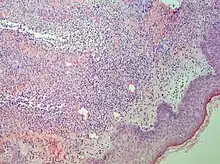

Punch biopsy of a skin lesion showing neutrophilic infiltration in the dermis, with no evidence of vasculitis (same patient with Crohn's disease).

Studies show a moderate neutrophilia (less than 50%), elevated ESR (greater than 30 mm/h) (90%), and a slight increase in alkaline phosphatase (83%). Skin biopsy shows a papillary and mid-dermal mixed infiltrate of polymorphonuclear leukocytes with nuclear fragmentation and histiocytic cells. The infiltrate is predominantly perivascular with endothelial-cell swelling in some vessels, but vasculitic changes (blood clots; deposition of fibrin, complement, or immunoglobulins within the vessel walls; red blood cell extravasation;inflammatory infiltration of vascular walls) are absent in early lesions.Perivasculitis occurs secondarily, because of cytokines released by the lesional neutrophils. True transmural vasculitis is not an expected finding histopathologically in SS.